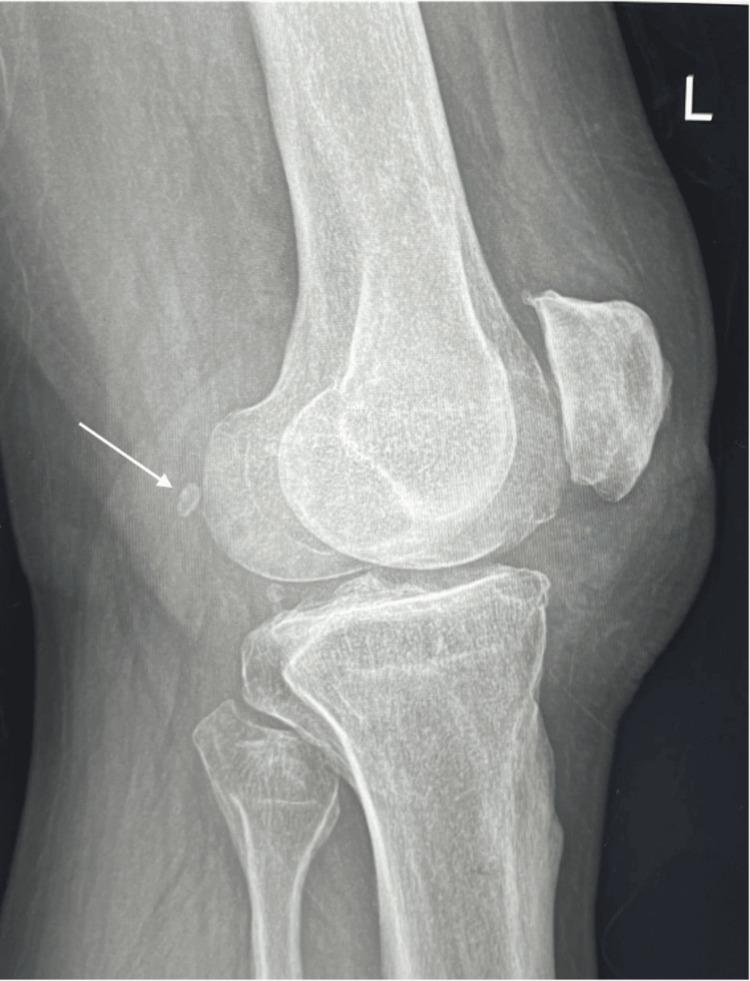

The Prevalence of Fabella and Its Association With Osteoarthritic Severity of Knee in Saudi Arabia: A Multicenter Study.

A retrospective multicenter study was conducted in AlAhsa, Saudi Arabia, reviewing knee X-rays of patients diagnosed with knee OA. Statistical analysis assessed potential associations between fabella presence, demographic factors, and OA severity using the Kellgren-Lawrence classification.

Among 348 participants, 96 (27.6%) exhibited fabella presence, with 38 (39.6%) of them showing fabellar degenerative changes. No significant associations were found between fabella presence and gender, age, knee side, or OA severity, except for a marginal trend in age groups. However, there was an increasing trend in fabellar degeneration with advancing OA grades.